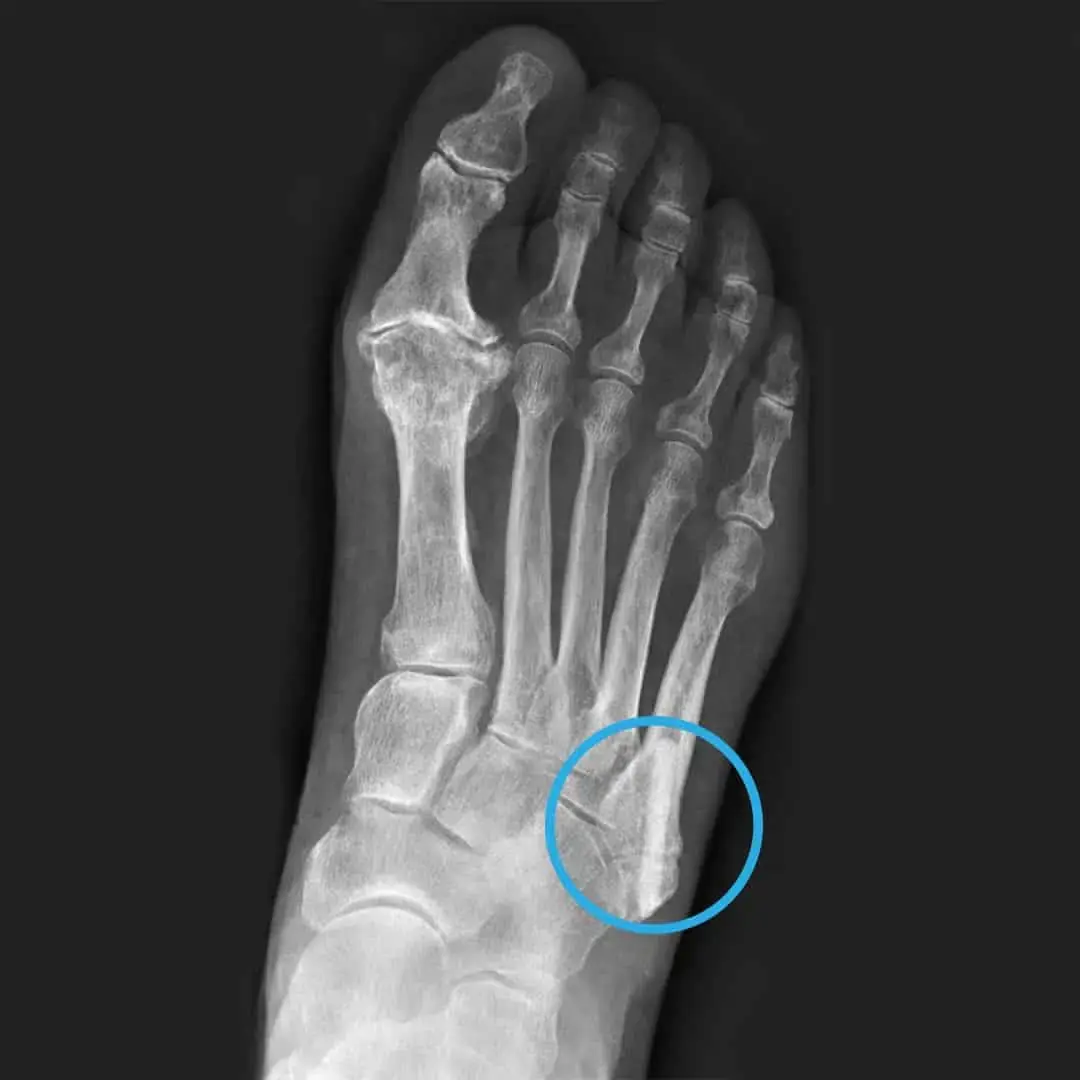

발가락 골절의 다양한 양상

발가락 골절은 흔히 발생하는 상황입니다. 이유는 다양하게 있을 수 있으며, 대표적으로는 실내에서 물건에 부딪히거나 높은 곳에서 떨어지는 등의 사고가 있습니다. 이 외에도 스포츠 활동 중 부상을 당하거나 교통사고 등에서도 발가락 골절이 발생할 수 있습니다. 발가락 골절은 크게 뼈가 완전히 부러진 경우와 뼈에 금만 간 경우로 나눌 수 있으며, 이에 따라 치료 방법과 기간이 다릅니다.